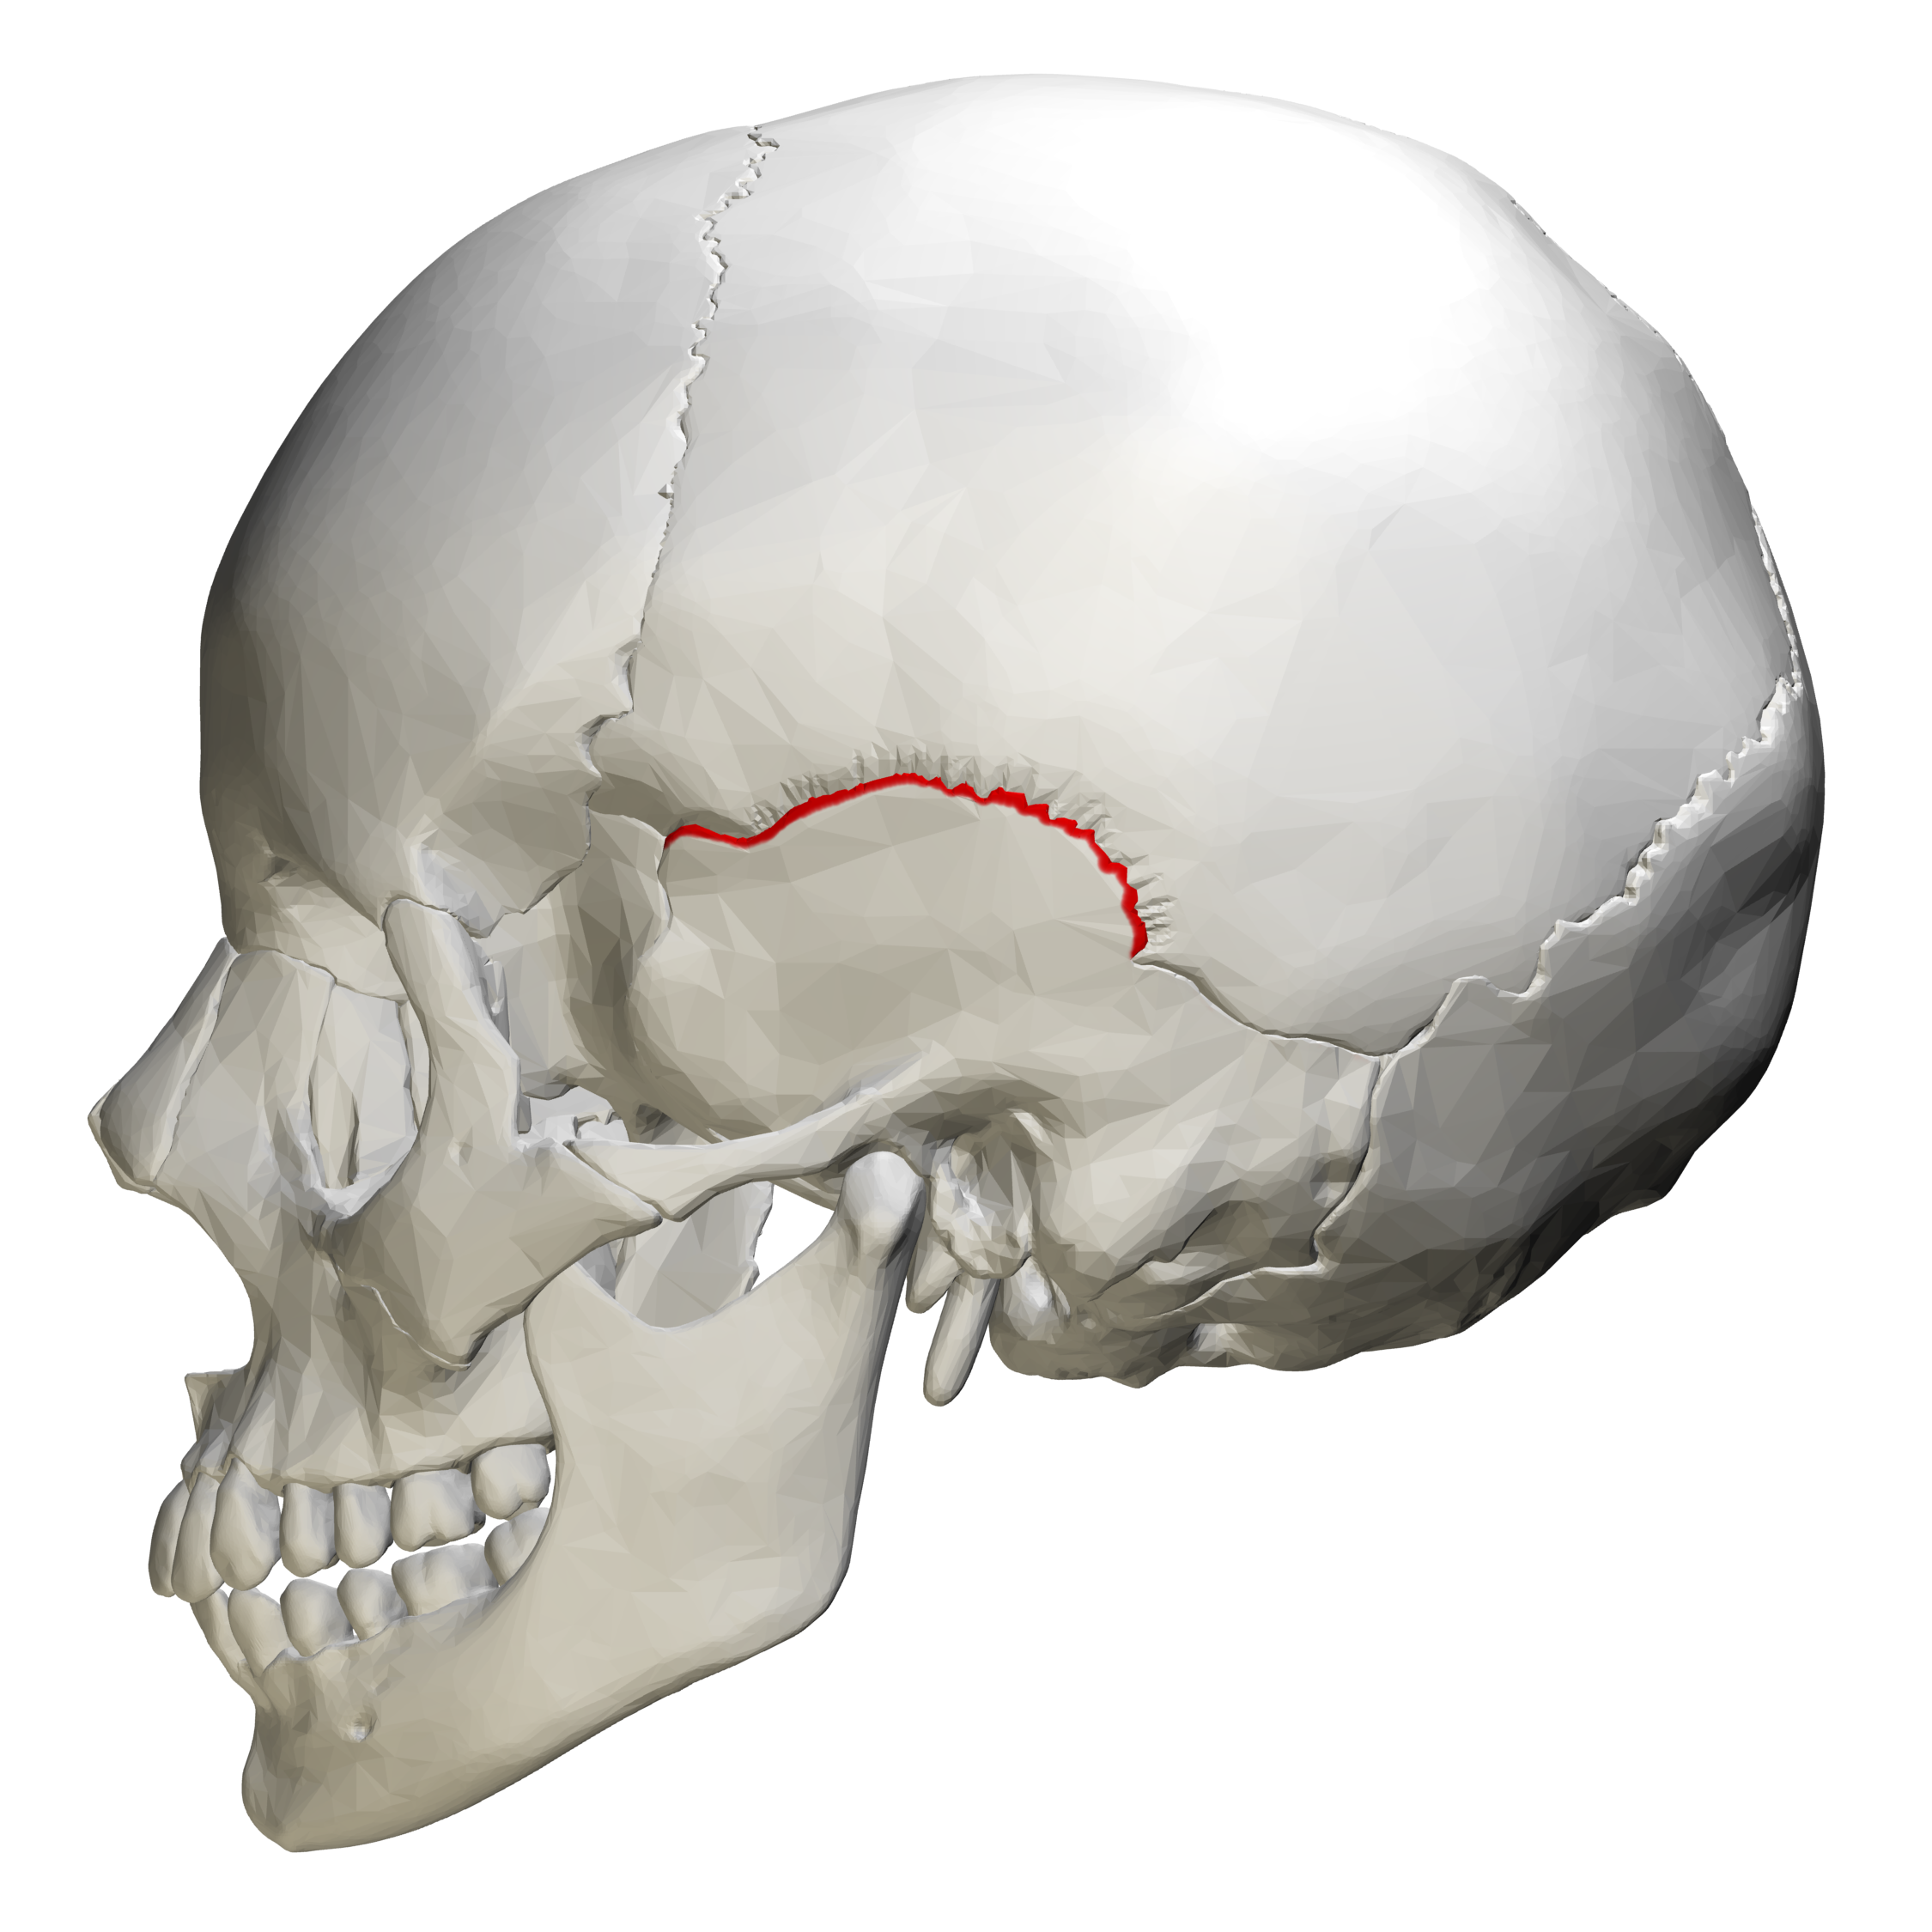

squamous suture